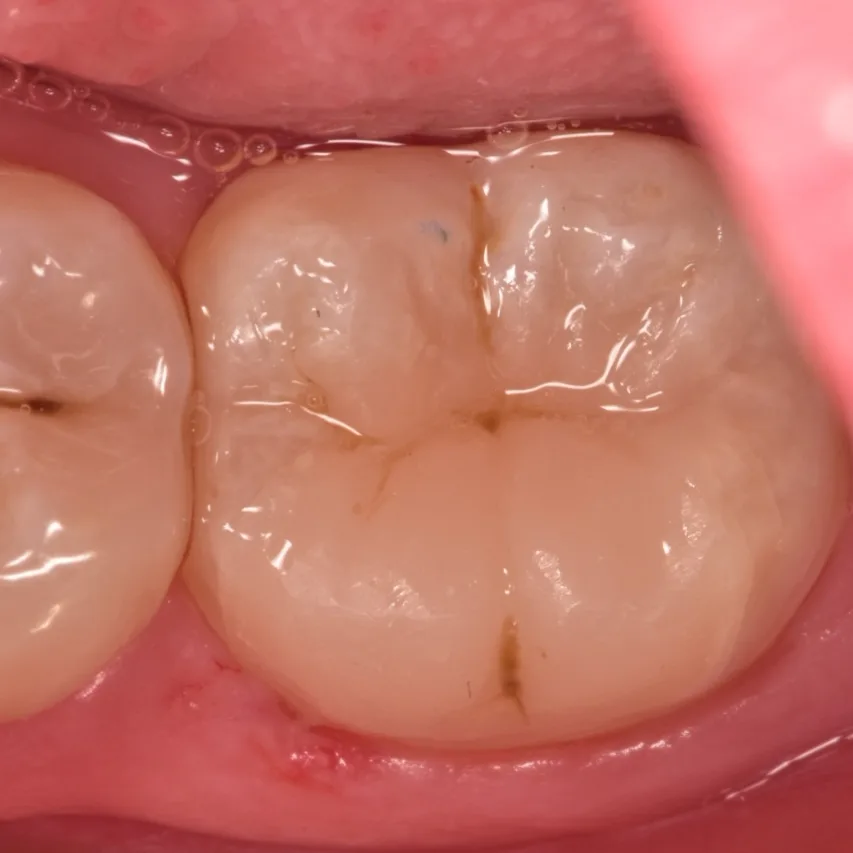

Occlusal view